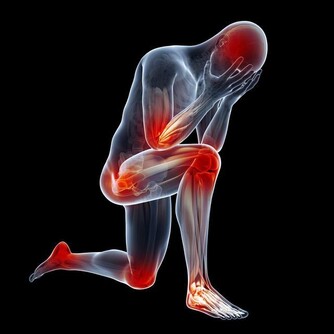

母親長年膝蓋總是出問題,「用洋蔥這樣做」之後不痛了,還可以出去慢跑!

膝蓋關節一直是諸多長輩的困擾,尤其到了中老年又缺乏運動的情況下,

很容易伴隨著天氣或者其他原因而不適...